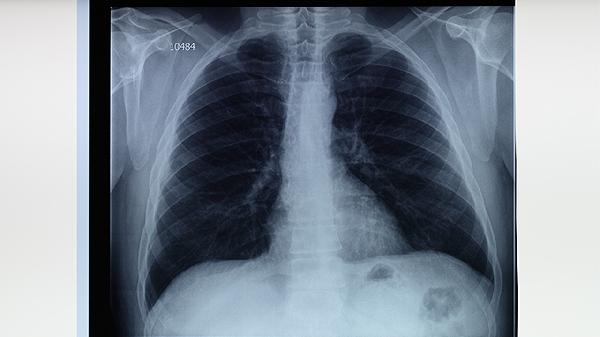

胸部X线检查是肺结核诊断的基本影像学方法,可发现肺部病变的位置、范围和性质。典型肺结核X线表现为上叶尖后段或下叶背段浸润性病变,可能伴有空洞形成。胸部X线检查有助于评估病情严重程度和治疗效果,但不能单独作为确诊依据。对于疑似病例,需要结合其他检查结果综合判断。